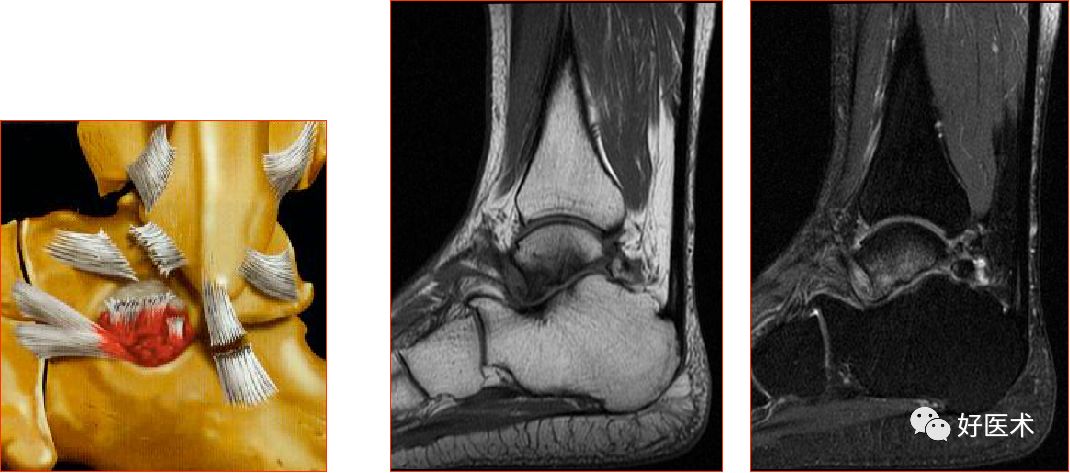

三、骨软骨病变

距骨骨软骨损伤,好发于前外侧、后内侧,尤其是后内侧,与内外翻损伤相关。

距骨骨软骨损伤分级